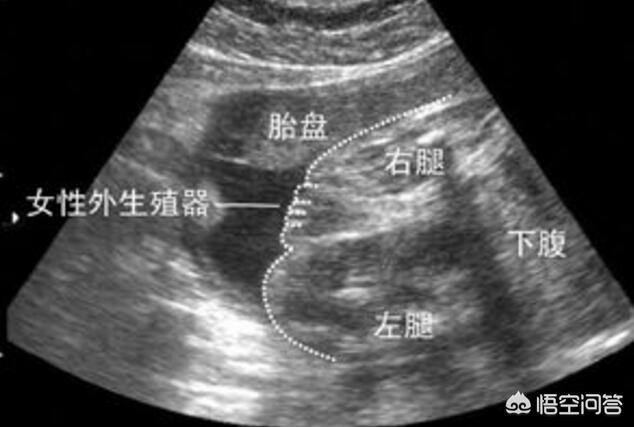

6个多月做B超 , 宝宝的私密部位已经看得非常确切了 , 医生也是人不是神 , 和我们一样有七情六欲、爱八卦 , 她想知道头胎是男孩还是女孩 , 好满足自己的好奇心 。